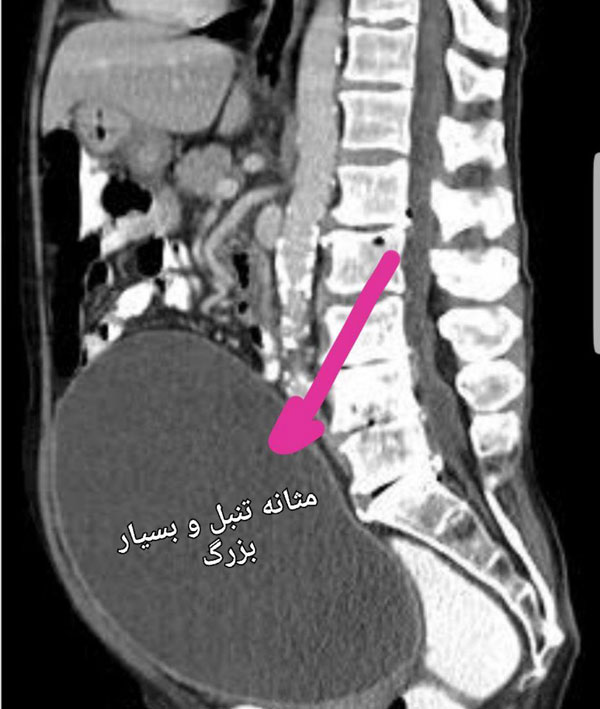

عکس سی تی اسکن در مثانه تنبل که بسیار بزرگ و ناکارآمد شده است.